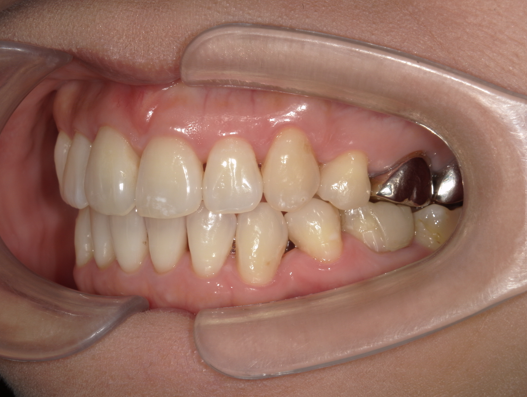

症例2:八重歯が気になる

| 患者様データ | 20代 女性 |

| 来院主訴 | 八重歯が気になる。 |

| 治療内容 | 八重歯を治すために上の親知らずを抜歯し、インビザラインにてマウスピース矯正を開始しました。かみ合わせを整えるためにゴムかけを行いました。 |

| 概算治療費 | 約85万円 |

| 治療期間 | 1年3ヶ月 |

| 通院回数 | 8回 |